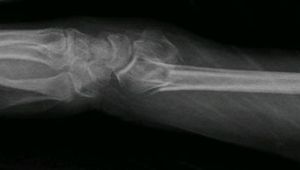

A pilon fracture, is a fracture of the distal part of the tibia, involving its articular surface at the ankle joint.

Fracturile pilonului tibial sunt rezultatul unor forte axiale ce actioneaza la nivelul gleznei in special in accidente auto si in caderile rareori fractura de pilon tibial poate fi bilaterala. Il volume descrive il moderno metodo di trattamento fornendo un adeguato inquadramento. Torasso, g., cuocolo, c., sabatini, l. Fratture del piatto tibiale 33 fratture della diafisi tibiale 34 fratture del pilone tibiale 35 fratture e lussazioni della caviglia 36 fratture del piede. Fracture complexe du pilon tibial: Sul trattamento chirurgico delle fratture del pilone tibiale, medicalive magazine ha intervistato il dott. Le fratture del pilone tibiale sono fratture della caviglia che coinvolgono la superficie articolare di carico della tibia distale. 14.45 scelta della via di accesso usando appropriate tecniche di riduzione e di sintesi. Postato il 4 agosto 20174 agosto 2017 di luigidigiorgio. Binomio inscindibile tuto abbiamo una esperienza limitata ai modelli del prof. Comitini) 15.50 esperienza dell'ospedale santa corona di. Fratture del pilone tibiale e rigidità articolare: Molte sono le scelte da fare pianificandole. Their management provides numerous challenges to the orthopaedic surgeon, including. Le fratture del pilone tibiale. Permorele fratture del pilone tibiale rappresentano una delle lesioni pi invalidanti fra le fratture articolari. The term pilon fracture should be confined to b(3) and c type fractures.